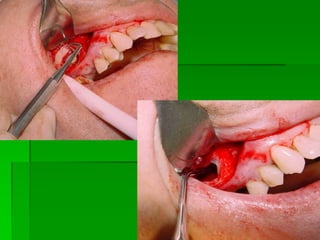

Áreas Doadoras Retro-molares

Enxertos de mento